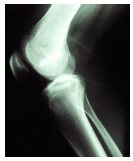

A questão a seguir, estão relacionadas com a imagem radiográfica abaixo:

A partir da anatomia radiológica demonstrada nessa imagem, é

CORRETO

afirmar que se trata da incidência

A

PA do joelho.

B

AP da perna.

C

AP do joelho.

D

perfil do joelho.